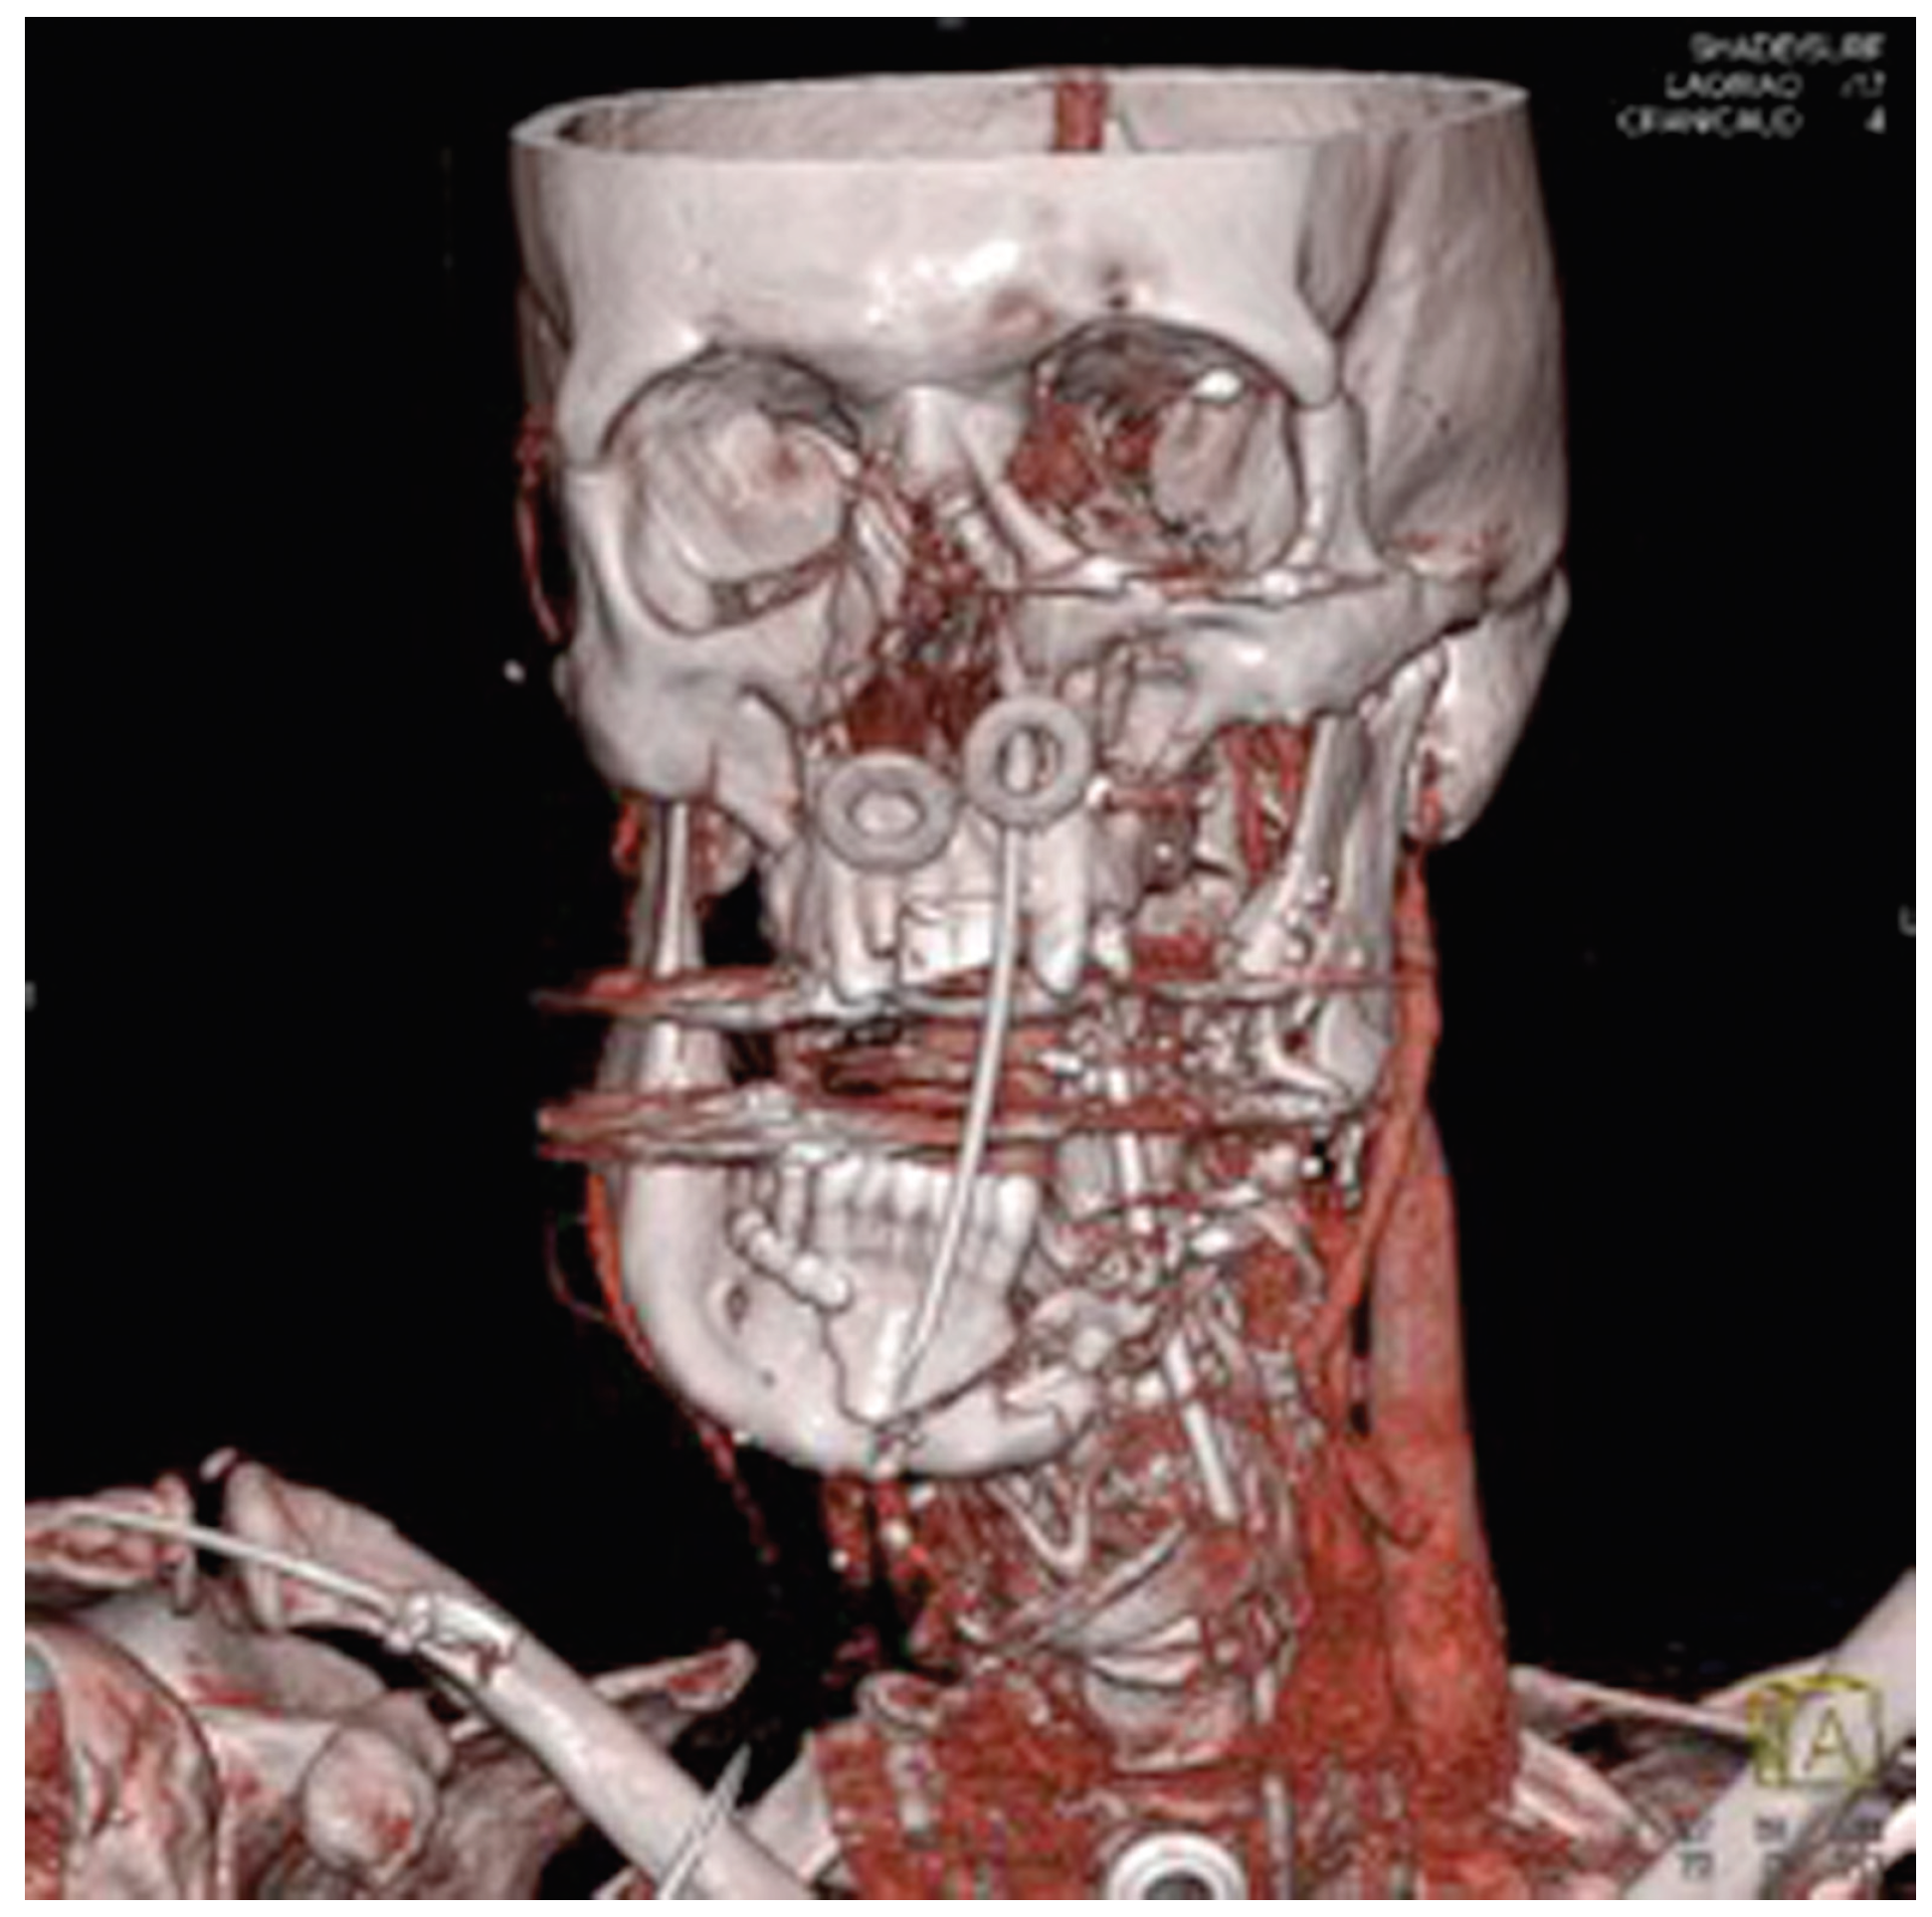

Figure 9.

Case 2. 3D-CT imaging of gun-shot wound to the face.